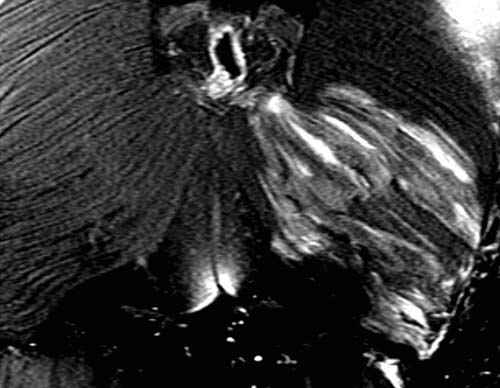

![]() |

In cases of strangling or throttling, a limited amount of pressure is exerted onto the cervical vessels, thus giving rise to petechial hemorrhages. However, they are rarely encountered in cases of classic suicidal hanging. In these cases, the afferent and efferent blood vessels to the head are typically-if the noose is behind the mandibular angle-equally compressed. Therefore, no petechial hemorrhages are to be expected. Here, a thorough medicolegal inspection can reveal telltale imprints to the neck, even if the noose has been removed. Slight and superficial abrasions of the skin can often lead to the correct diagnosis. Additional hemorrhages of the subcutaneous tissue and the cervical musculature can, according to our experience, further support this hypothesis (Figure D3.2.18), although recent literature is uncertain as to the overall significance [17,18]. Furthermore, fractures of the hyoid bone or thyroid horns, a finding easily detected in postmortem MSCT (Figure D3.2.19 and Figure D3.2.20), give rise to the diagnosis blunt trauma to the neck [19,20].

Postmortem imaging, especially in the form of MRI, can visualize such lesions that would otherwise only be detected at autopsy. The pathology and forensic imaging of choking is dealt with in further detail in Chapter D3.7, "Strangulation." Obviously, osseous lesions are easily seen in postmortem MSCT. Hyoid and thyroid fractures can give clues as to whether a blunt trauma occurred to the neck. A caveat is nevertheless to be made: Anatomical variations of the thyroid and hyoid structures may give the impression of such violent injuries. In these cases, a surrounding hemorrhage-as found in traditional autopsies-must be looked for. The lack of such hemorrhages in postmortem imaging deems a vital or fresh fracture of the throat skeleton rather unlikely.